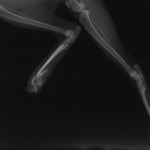

症例3:キルシュナーワイヤーのピンニングによる整復

ペルシャ猫 11ヶ月齢 雄

他院にて左大腿骨遠位の成長板骨折(salter-harrisⅠ型)が認められており、治療相談を目的として来院。当院にて、キルシュナーワイヤーを用いたピンニングにより骨折部位の整復を行いました。術後の経過は良好で、現在も経過観察中です。

術前レントゲン

術後レントゲン

機器

Arthrex社のターゲティングデバイスを用いてピンニングの位置を調整することで、確実な固定を行っています。当院ではこの手術器具以外にも、人の手術にも使用される様々な器具を導入し、手術精度を高め、また医療メーカーと新しい器具の開発、試作にも取り組んでおります。